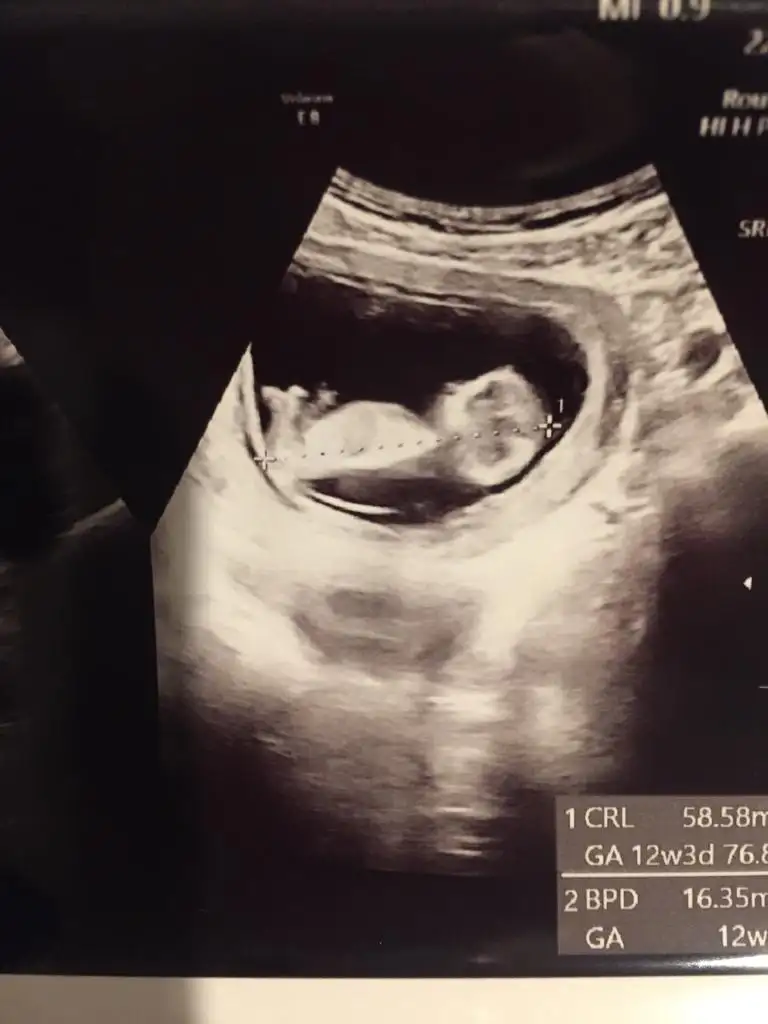

sen de uzulme artik nolur. Çok şükür simdi saglikli bir gebeligin var. Allahim saglik sihatle kucagina almayi nasip etsin

. Guzel haberler alalım minnosundan